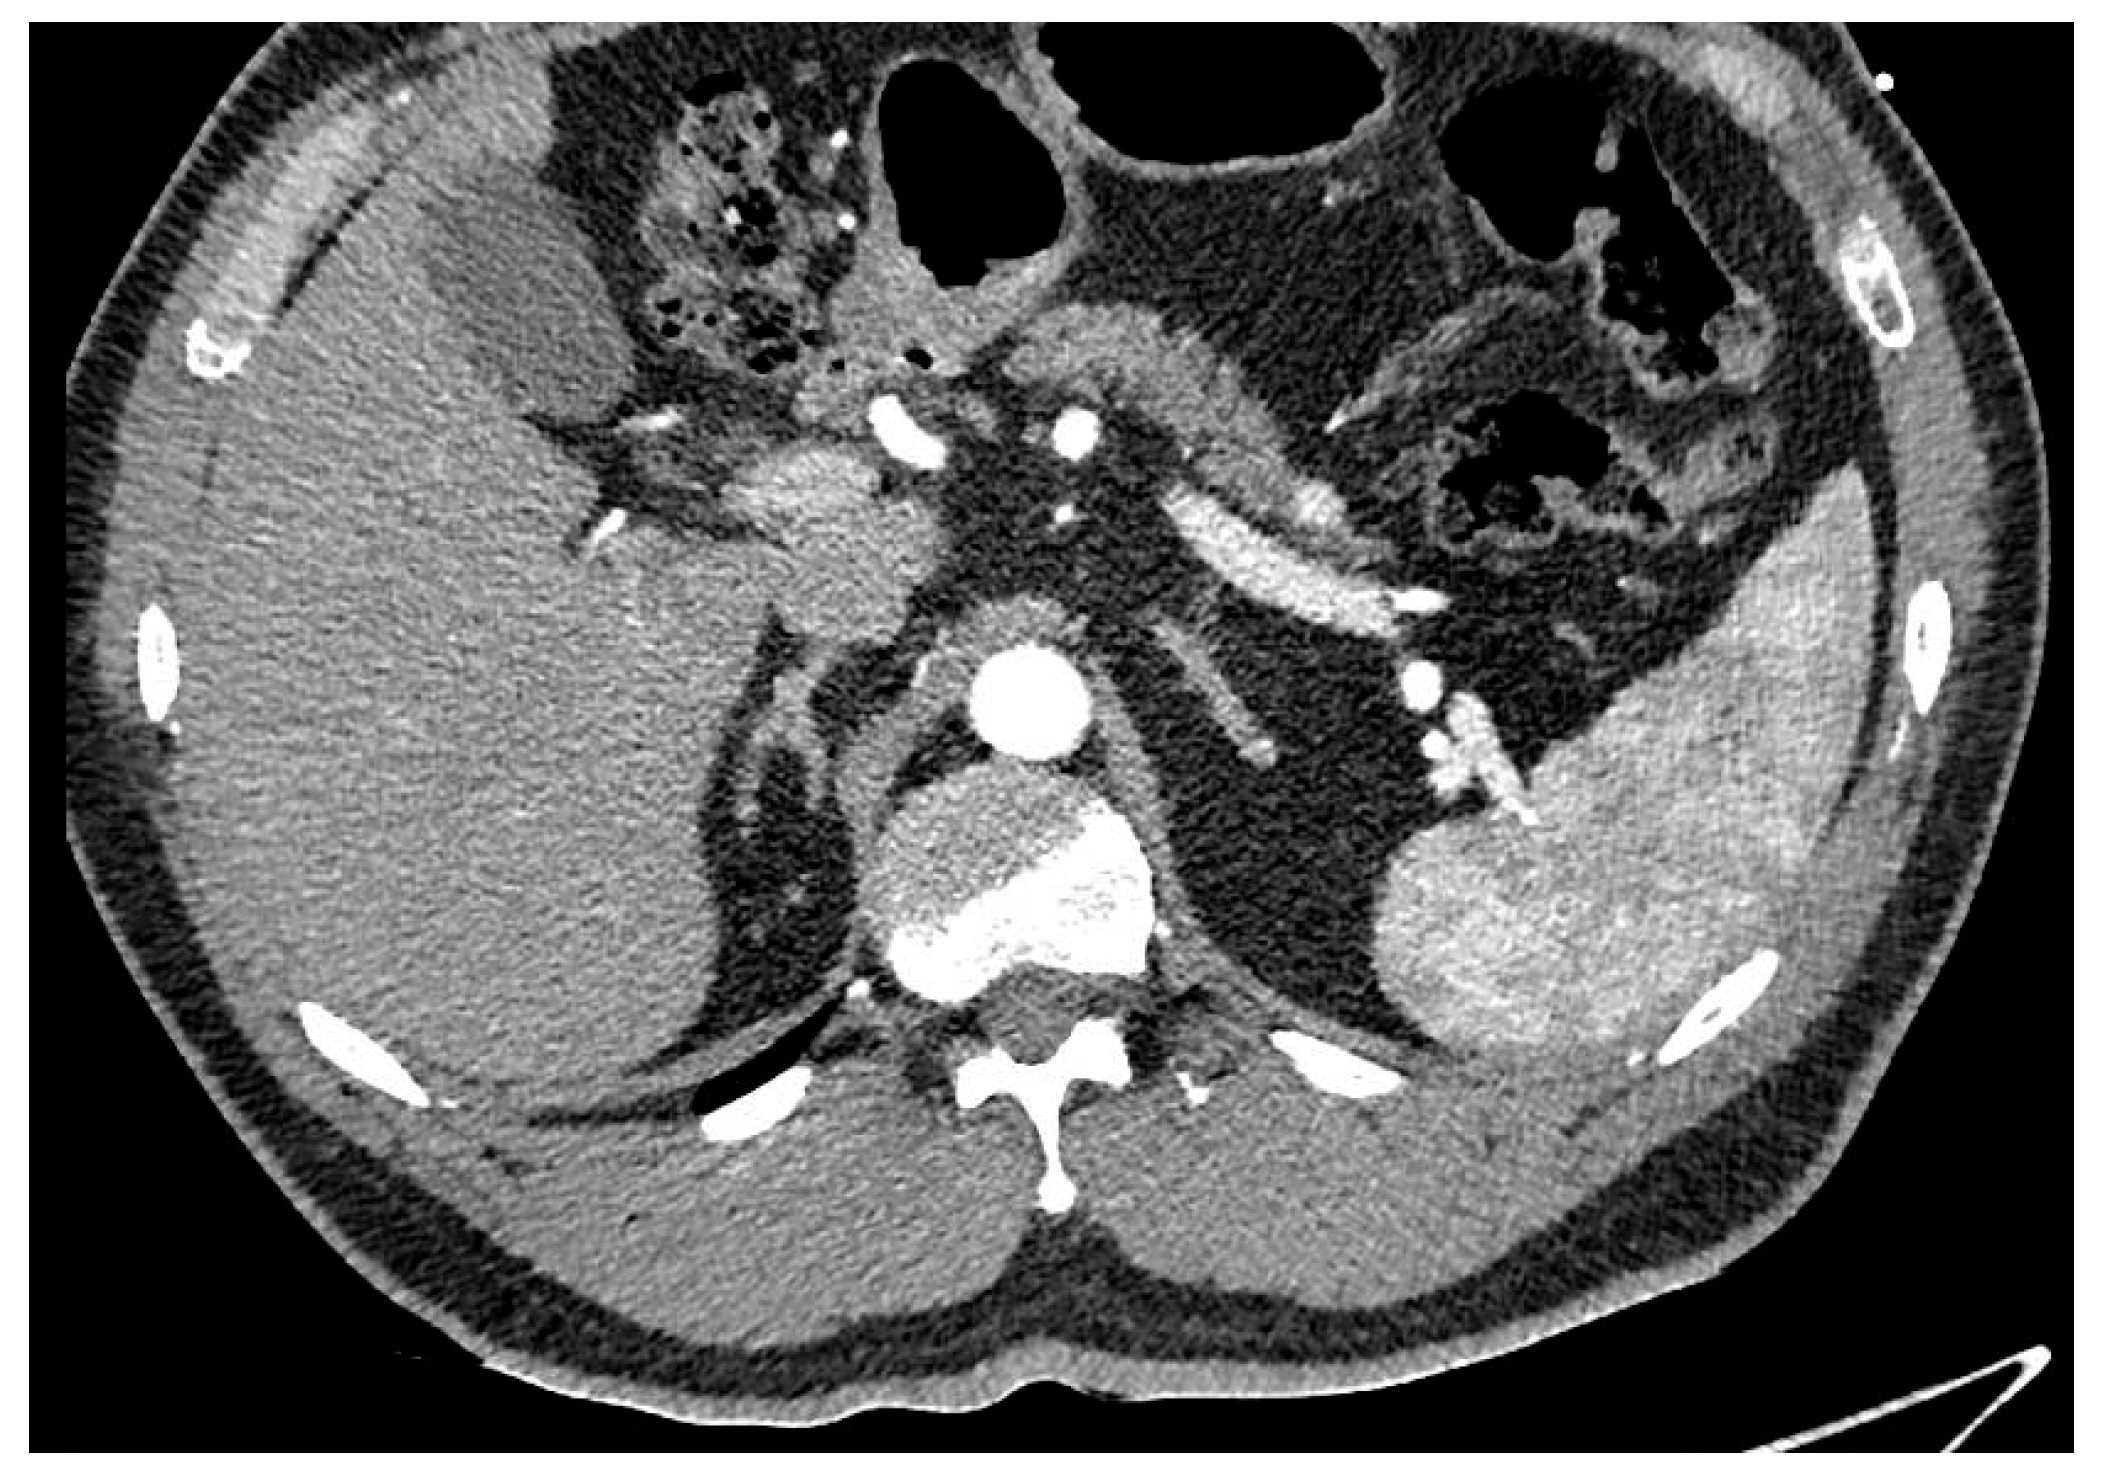

Pancreatic ductal adenocarcinoma (PDAC) is an aggressive form of cancer that carries a poor prognosis. PDAC usually occurs in the head of the pancreas. It is estimated that between 80 and 85% of PDAC lesions are advanced and irresectable, or non-curable, at presentation. This is mainly because the symptoms that patients experience can be vague and non-specific, like abdominal pain, and the symptoms can be challenging to diagnose, leading to delays in diagnosis. See Figure 2.

Figure 2. Hypodense lesion in the head of the pancreas, biopsy adenocarcinoma treated with Whipple.